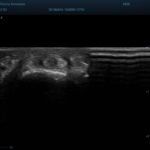

Lesione della cuffia dei rotatori

Paziente con dolore alla spalla dx,all’es.ecografico versamento nella borsa subacromialee lesione del tendine sovraspinato ben evidente anche se piccola L’esame ecografico ha il vantaggio rispetto alla risonanza magnetica che è dinamico,si fa anche muovendo attivamente e passivamente l’articolazione dlela spalla